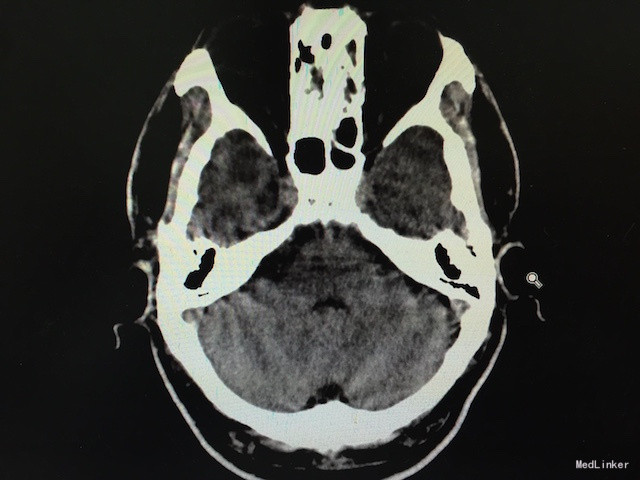

查体:右侧面部疼痛诱发有明显的扳机点,累及三叉神经1、2、3支;感觉无明显异常,四肢肌力、肌张力可;病理征(-)。 辅助检查:头颅CT未见桥脑角区明显占位。

随访及讨论:术程顺利,术后患者恢复出院,术后病理回报为胆脂瘤,无听力减退等术后颅神经损伤并发症。一般胆脂瘤压迫导致的三叉神经痛,CT平扫显示不明显,且症状并不典型,常规行头颅MRI不现实,故对于这类由于继发性因素引起的三叉神经痛,术中可以诊断及去除病因。